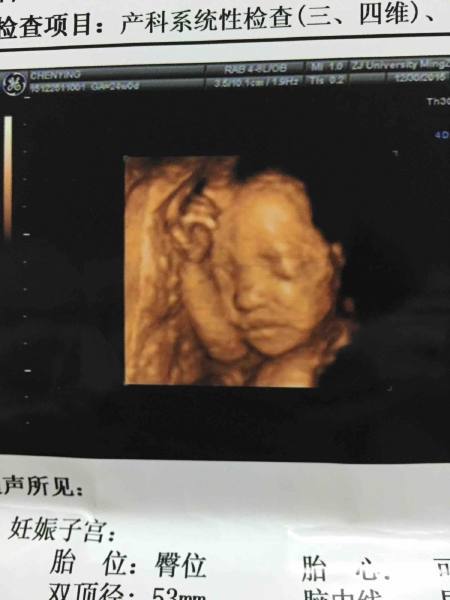

宝宝四维它俗柴图片怪神来了,怎么一点都不像我?翘嘴巴也不知道兵北像谁,

宝宝还偏小10天,今天24周了,检查出来才22周加3,有和我一样的吗?